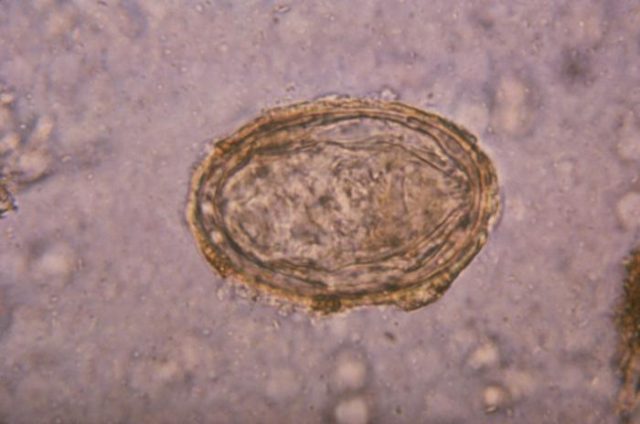

The infection comes from a type of microscopic trematode worm called Schistosoma, which has a complex life cycle. Just as the malaria parasite spends part of its life inside a mosquito, Schistosoma need a secondary host, in this case water snails, inside which their babies grow into teenagers. Now we get to the really gruesome part.

Once in the system, the Schistosoma migrate through their victim’s bloodstream to the liver, where they grow into adults and mate, before wiggling off to the intestines or bladder (depending on the species) to lay their eggs. The eggs leave the body by way of urine or feces, then hatch into larvae which start hunting for a water snail. And the terrible cycle begins again.